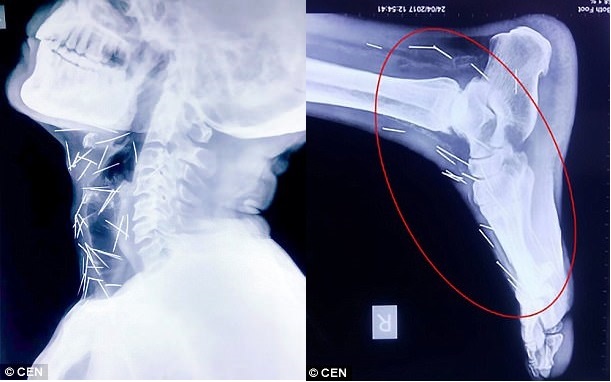

Một người đàn ông Ấn Độ đang làm việc cho một công ty đường sắt phải nhập viện để lấy hàng chục chiếc kim trong cơ thể.